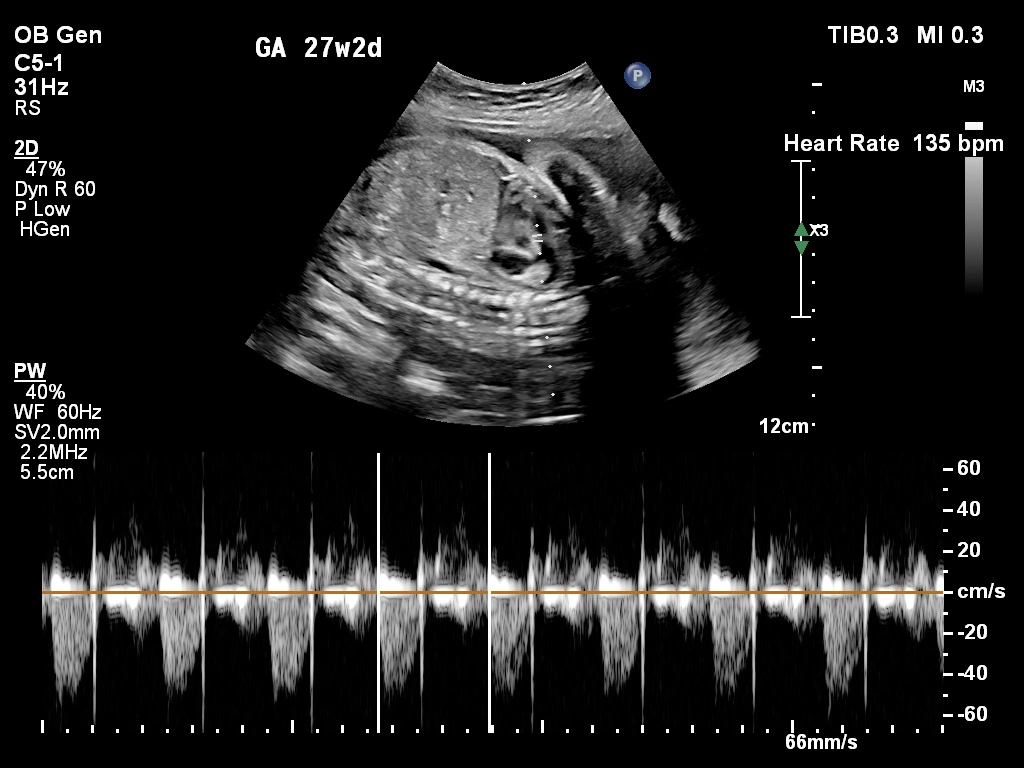

🔹 Fetal Echo / Adult Echo (Echocardiography)

Echo (Echocardiography) is a specialized ultrasound used to examine the heart. Fetal Echo evaluates the baby’s heart structure and function during pregnancy, while Adult Echo checks heart health in adults. It helps detect congenital heart defects, valve problems, and blood flow issues. If you need a fetal echo in Kathmandu, this test plays a vital role in early diagnosis and treatment planning.